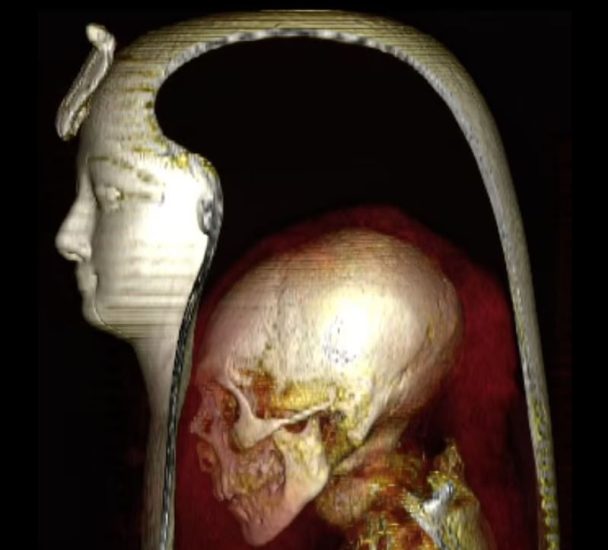

Ekspertët e udhëhequr nga Universiteti i Kajros, ishin në gjendje të përdornin tomografinë e kompjuterizuar (CT) për të krijuar pamje 3D të burrit poshtë fashave. Ata zbuluan se faraoni ishte 35 vjeç kur vdiq rreth tre mijëvjeçarë më parë.

“Fakti që mumja e Amenhotep I nuk ishte zbuluar kurrë në kohët moderne, na dha një mundësi unike,” shpjegoi aerkologu Sahar Saleem nga Universiteti i Kajros.